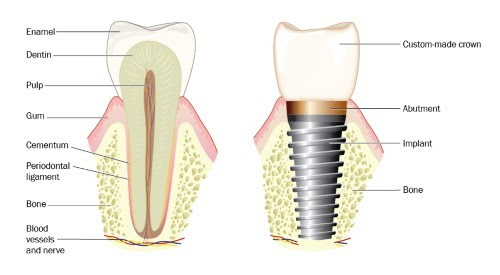

Dental implants are one of the biggest and most successful advances in modern dentistry. They are an effective, long-term option if you have missing teeth or wear dentures that are uncomfortable. An implant is a small, titanium root-shaped screw that is inserted into the jawbone to replace a missing tooth or to help retain dentures. The implant fuses with the bone and healing is usually completed within 3-4 months. This provides a solid foundation for an abutment and dental crown. The implant looks, feels and acts like a real tooth, and if properly cared for, can last a lifetime.